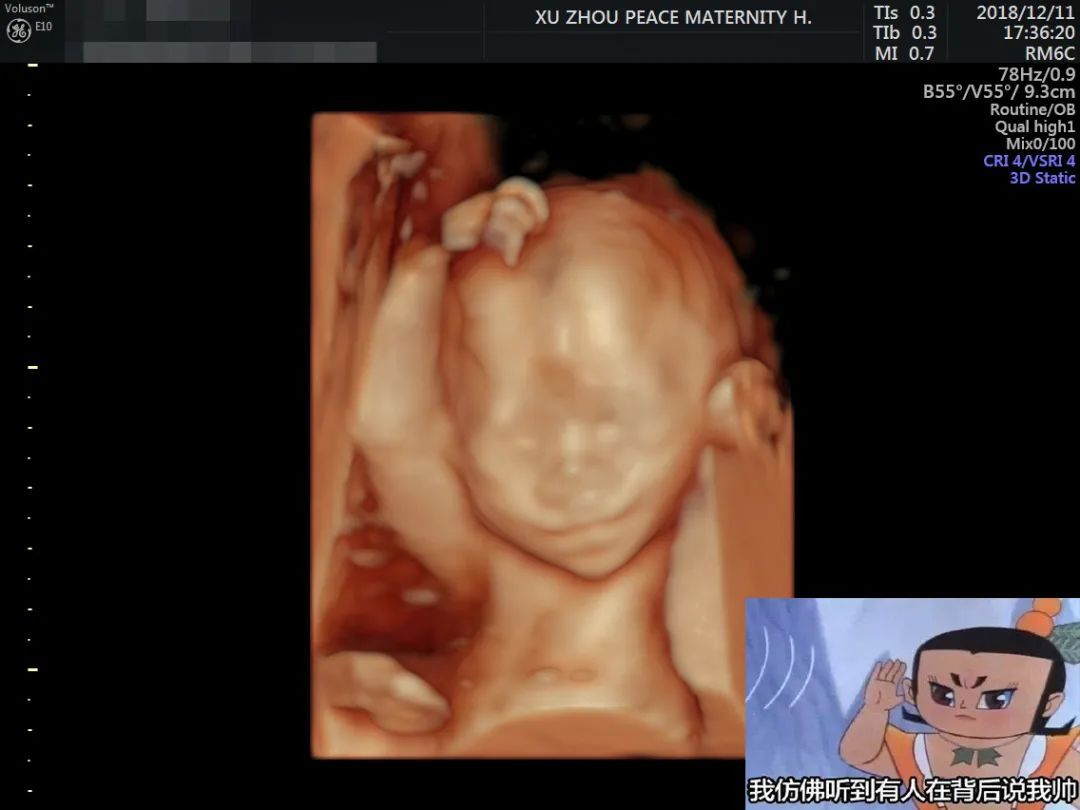

胎位调整,瞬见“正脸”

做过四维的妈咪都知道,要是刚好碰到宝宝趴着身子或是捂着小脸,妈妈们可就免不了狂吃甜食或来回运动、爬楼梯的一番折磨

。

助产士会根据准妈妈自身情况,运用专业医疗手法个性化调整孕妈胎位,帮助妈妈们一次看清宝宝正脸!

和平妇产医院引进的美国GE-E10四维彩超,提供更多、更科学的图像数据,实现胎儿影像的全方位动态演示,颠覆传统视觉理念,精准排畸不负众望!